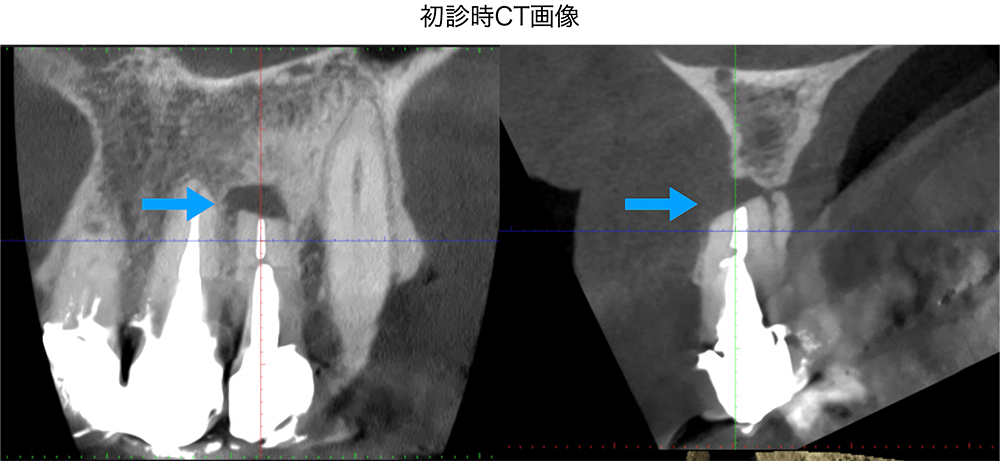

金山デンタルクリニックでは、治療の前に必ずCT撮影を行い、神経の本数や根の形、病変の大きさを正確に診査。治療の可能性や成功率まで含め、CTの画像を見せながら丁寧にご説明しています。治療後の経過もマイクロスコープやCT画像をお見せしながら、ご説明させていただきます。